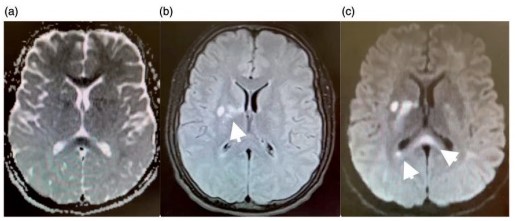

Asimismo, una investigación encontró patrones comunes de lesiones cerebrales a través de la neuroimagen mediante una recopilación extensa de estudios radiológicos vinculados con casos de adolescentes con problemas de adicción a sustancias psicoactivas ilegales, desde 2006 hasta 2016. El estudio constató dos patrones coincidentes. El primero fue la lesión cerebral difusa simétrica de la sustancia blanca subcortical con afectación cerebelosa preferencial, o leucoencefalopatía. El segundo lo constituyen múltiples focos de infartos isquémicos en una distribución territorial no arterial patrón isquémico.(21)

En esta investigación que se viene señalando, se puede mencionar el caso de un joven de 16 años, con alteración aguda del estado mental por inhalación de vapor de heroína. Se le efectuó una RM que evidenció hiperintensidades en T2 de la sustancia blanca simétrica difusa infratentorial y supratentorial. El diagnóstico clínico en este caso fue rabdomiólisis, que afecta predominantemente la musculatura posterior del cuello(21) (ver Imágenes 11 y 12).

Otro caso que merece ser comentado es el de un adolescente de 15 años que presentó encefalopatía y signos extrapiramidales por ingestión de metadona. La RM evidenció focos de infartos agudos en el caudado y putamen, así como infartos corticales de la línea divisoria de aguas parietales(21) (ver Imagen 13).